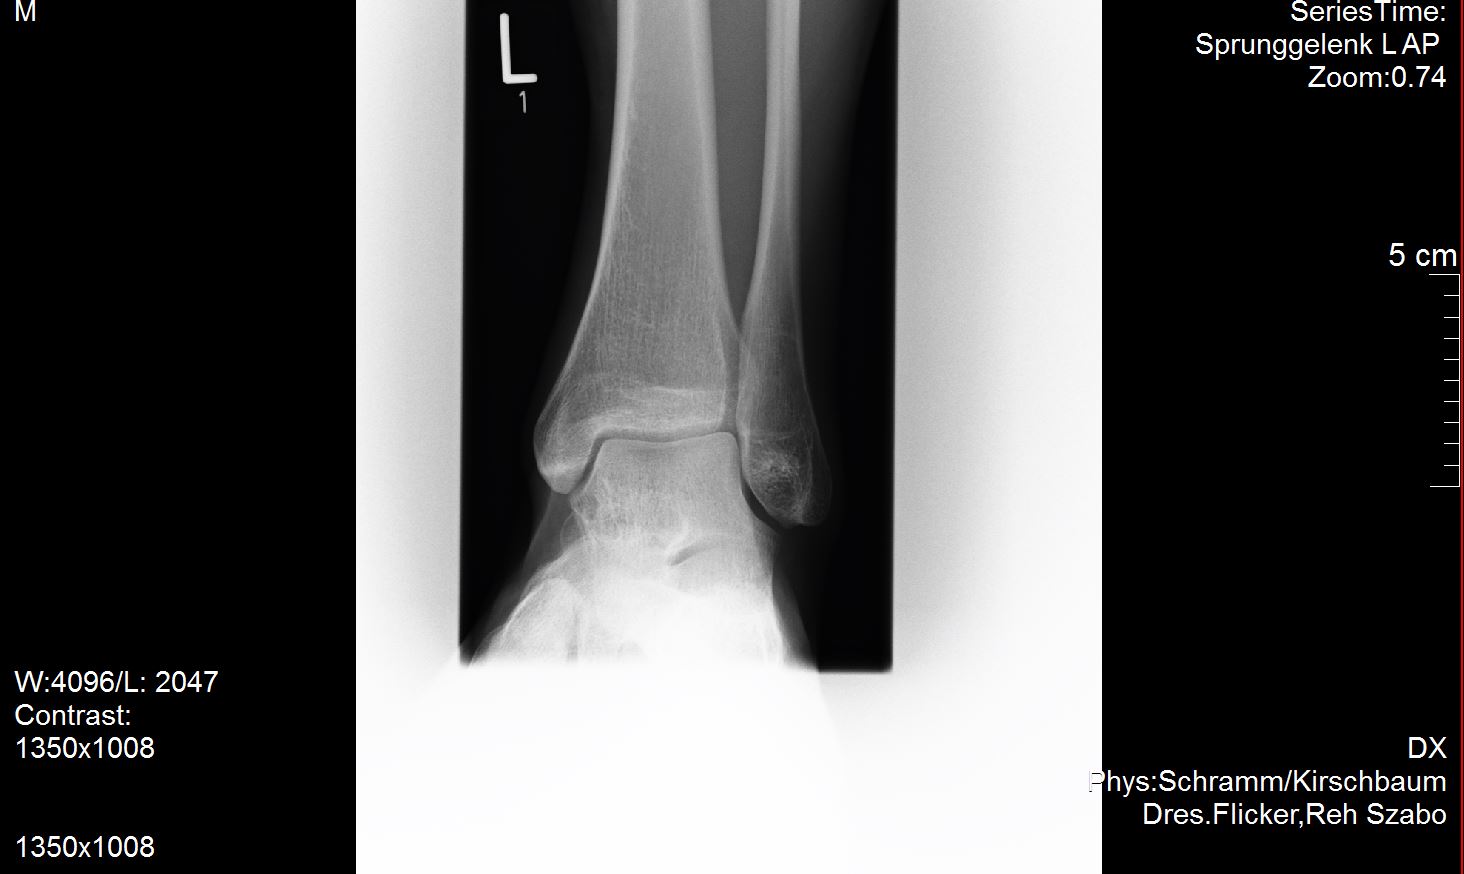

Ich versuche mal meine Röntgenbilder anzuhängen. Vielleicht ist ja ein Experte unter uns der dazu was sagen kann?

Ich habe außer dem mir diagnostizierten Spreizfuß nach oben stehende Zehen. Weiß nicht genau ob man dies Hammerzeh oder Krallenzeh nennt was ich habe aber es geht in die Richtung.